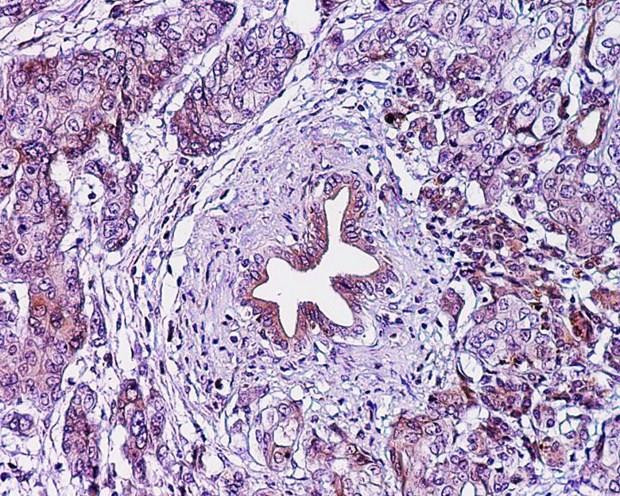

Điều chỉnh 2 loại enzyme có thể giúp điều trị ung thư tuyến tụy ảnh 1Lớp cắt biểu bì ung thư tuyến tụy. (Nguồn: eurekalert.org)

Ung thư tuyến tụy do sự phát triển bất thường và không kiểm soát được của các tế bào trong tuyến tụy, một tuyến lớn trong hệ tiêu hóa, gây ra.